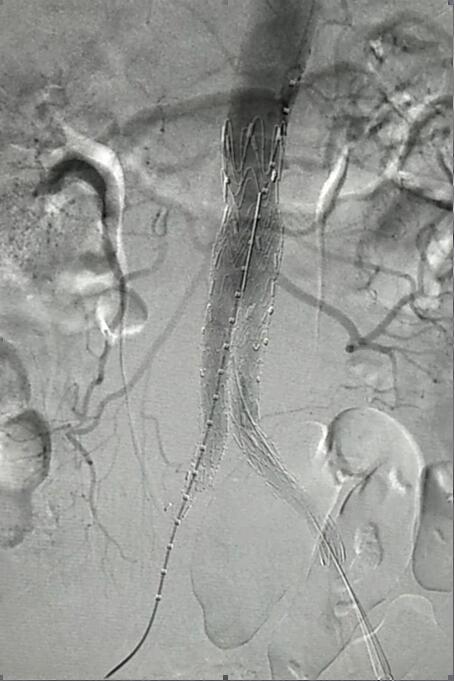

血管介入科行腹主動脈瘤覆膜支架隔絕術(shù)(“褲衩”支架植入)。圖2

患者因腹部搏動性腫塊行成已有4年,伴右下腹疼痛6小時入院,既往有高血壓病史,患者入院后血壓177/96mmHg,醫(yī)護(hù)人員隨即予以控制血壓、止痛處理,CTA檢查提示患者有腎下腹主動脈瘤,合并心 、肝 、肺 、腎等重要臟器疾患,根據(jù) Laplace定律,動脈瘤直徑越大壓力越大,老人動脈脆弱,動脈瘤隨時有破裂的可能性,其危險性大。血管介入科排除各種困難,在麻醉科協(xié)作下行腹主動脈瘤覆膜支架隔絕術(shù)(“褲衩”支架植入),手術(shù)持續(xù)了1個半小時,患者術(shù)后安返病房,麻醉醒后露出了微笑,向醫(yī)務(wù)人員伸出大拇指。